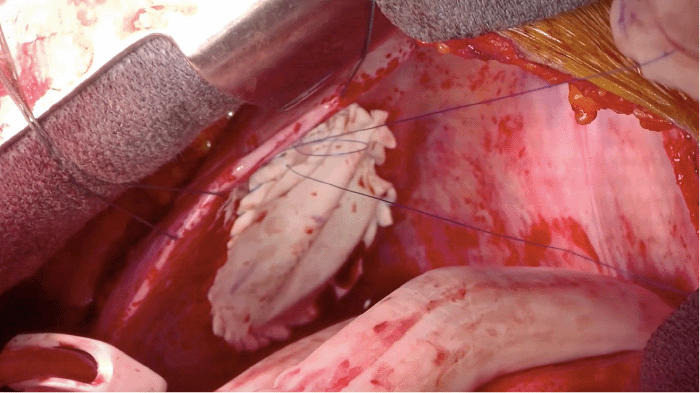

Intraoperatively, a large, preexisting left-sided pericardial defect was discovered, with herniation of the left ventricle through the defect (Figure 3). The defect was well-circumscribed with smooth edges, inconsistent with an acute tear (i.e., rupture) but indicative of a chronic rather than acute process. Following reduction of the herniated left ventricle, a clear demarcation line was observed where the pericardial defect had been compressing the coronary vessels (Figure 4). The extent of permanent damage to the coronary arteries remained uncertain.

Figure 3. Intraoperative View. Published with Permission

Edge of the pericardial defect (arrows); the left ventricle is visibly protruding through the defect.